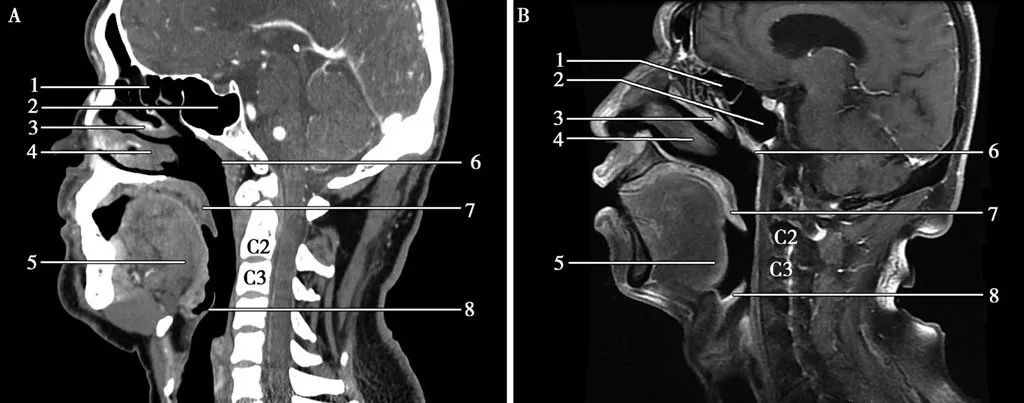

▲矢狀面(miàn)-鼻咽層面(miàn)A.CT;B.MRI

鼻咽癌表現爲鼻咽部軟組織腫塊,病竈大小不等,早期腫塊不明顯,僅表現爲咽隐窩變淺,腭帆提肌腫脹,晚期表現爲突出鼻咽腔的腫塊,大者可占滿鼻咽腔,形态不規則,可侵犯鄰近結構,沿顱底孔道(dào)蔓延至顱内。影像學(xué)檢查對(duì)确定腫瘤侵犯範圍及與周圍重要結構的關系十分關鍵。在區别腫瘤和軟組織,評估淋巴結轉移,觀察腫瘤沿神經(jīng)擴散和骨髓受累方面(miàn),增強MRI優于CT掃描。CT掃描可以更好(hǎo)地顯示早期顱底骨質破壞和其他的骨質破壞征象。

CT表現:鼻咽癌局限在黏膜間隙時(shí),CT表現爲鼻咽腔兩(liǎng)側不對(duì)稱,局部黏膜增厚,一側咽隐窩變淺或消失,腭帆提肌、腭帆張肌腫脹,脂肪間隙消失。可引起(qǐ)周圍結構的侵犯:向(xiàng)前侵犯鼻腔,達翼腭窩,向(xiàng)兩(liǎng)側侵犯咽旁間隙,向(xiàng)後(hòu)侵犯咽後(hòu)間隙以及椎前肌,向(xiàng)下侵犯口咽軟腭和扁桃體,向(xiàng)上侵犯斜坡及顱底骨質,通過(guò)顱底孔道(dào)進(jìn)入顱内。鼻咽癌常并發(fā)頸部淋巴結腫大。CT增強掃描,腫塊輕度強化,邊界不清(下圖)。

MRI表現:MRI顯示腫瘤範圍、周圍結構侵犯以及頸部淋巴結腫大與CT基本相同,因MRI軟組織分辨率較CT高,所以MRI能(néng)更早的發(fā)現病變,并準确地顯示病變部位、大小、範圍及浸潤深度。T1WI上腫塊相對(duì)于肌肉呈低-等混雜信号,T2WI呈較高信号,增強後(hòu)輕度強化(下圖)。